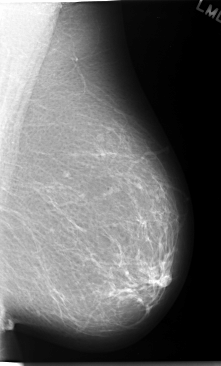

C_0057_1.LEFT_MLO

LEFT_CC LINES 5976 PIXELS_PER_LINE 3680 BITS_PER_PIXEL 12 RESOLUTION 50 NON_OVERLAY

LEFT_MLO LINES 5848 PIXELS_PER_LINE 3536 BITS_PER_PIXEL 12 RESOLUTION 50 NON_OVERLAY